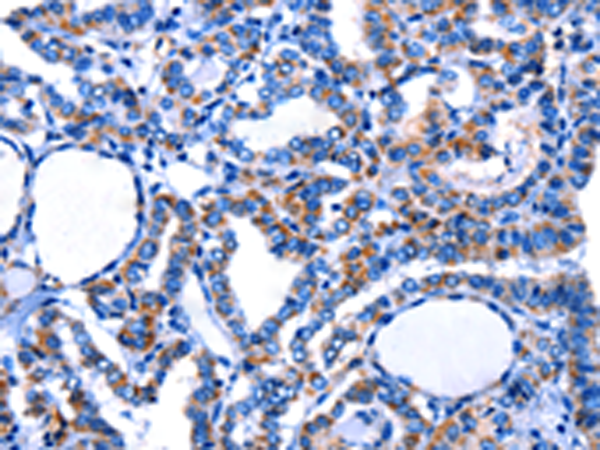

分类: 科研抗体货号: P00273别名: CaCC; CaCC2应用: WB,IHC反应种属: Human, Rat